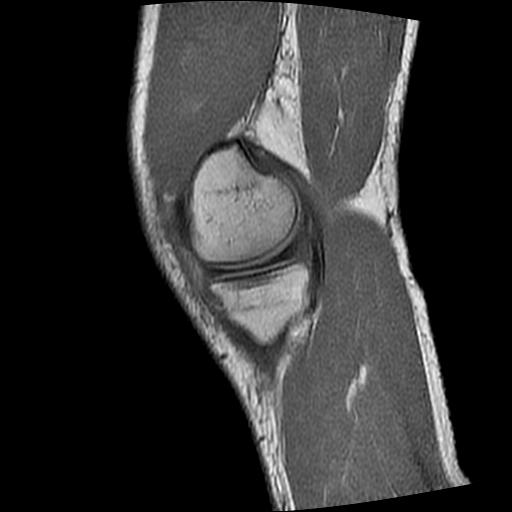

40岁男性,右膝关节外伤,x光平片示,髁间隆突撕脱骨折。

1、前交叉韧带撕裂;

2、外侧半月板后角撕裂;

3、关节腔积液。

前交叉韧带撕裂,关节腔积液.

半月板1-2级损伤   前交叉韧带撕裂伤   关节腔少量积液  诸骨未见新鲜外伤性改变

髁间隆突撕脱骨折;内侧副韧带损伤。

内侧副韧带撕裂及关节腔积液是肯定的,但是前交叉撕裂确定吗?会不会有容积效应的因素,因为前一张前交叉显示清楚,连续性良好,且较光滑。请问楼主有关节镜支持吗?我们医院也经常有这样的患者,但苦于没有关节镜,而无法对照、证实(除非完全断裂),出现了不同的诊断结果只能毫无意义的争论。

1、前交叉韧、内侧副韧带撕裂;

3、关节腔积液。4、髁间脊撕脱骨折。

除了关节积液外并无韧带撕裂,acl胫侧附着点有2束,正常情况下脂肪信号。此病例应加做压脂像以便观察是否有骨损伤。